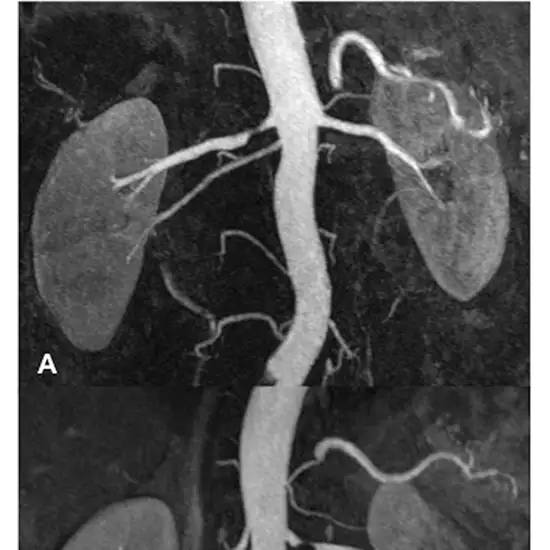

MR Angiography Renal enables accurate evaluation of renal artery stenosis by imaging the kidneys' blood arteries.

MR Angiography Renal Arteries is an imaging diagnostic tool that is used to look for the conditions of the renal arteries. Patients should not avoid any symptoms related to renal artery abnormalities or disorders. Patients should go for screening to avoid any delay in diagnosis and treatment of  MR Angiography Renal Arteries.